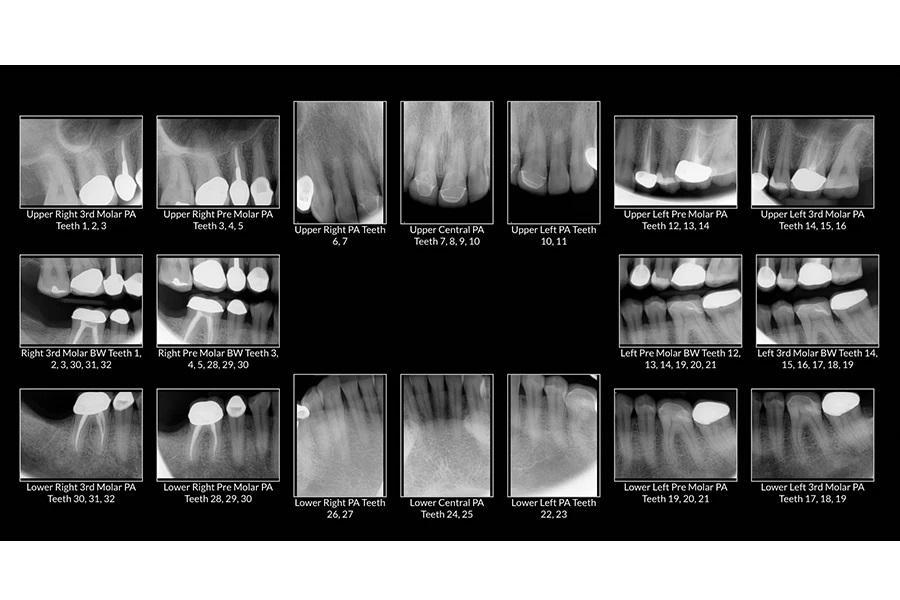

Пародонтологический статус: В области боковых зубов горизонтальная потеря костной ткани составляла менее 2 мм, глубина зондирования — до 3 мм, без кровоточивости. При клинической потере прикрепления менее 2 мм пациентка классифицирована как стадия I, степень A по классификации Американской академии пародонтологии (AAP) (фото 5).

Фото 5. Рентгенологическая серия всей полости рта до лечения.